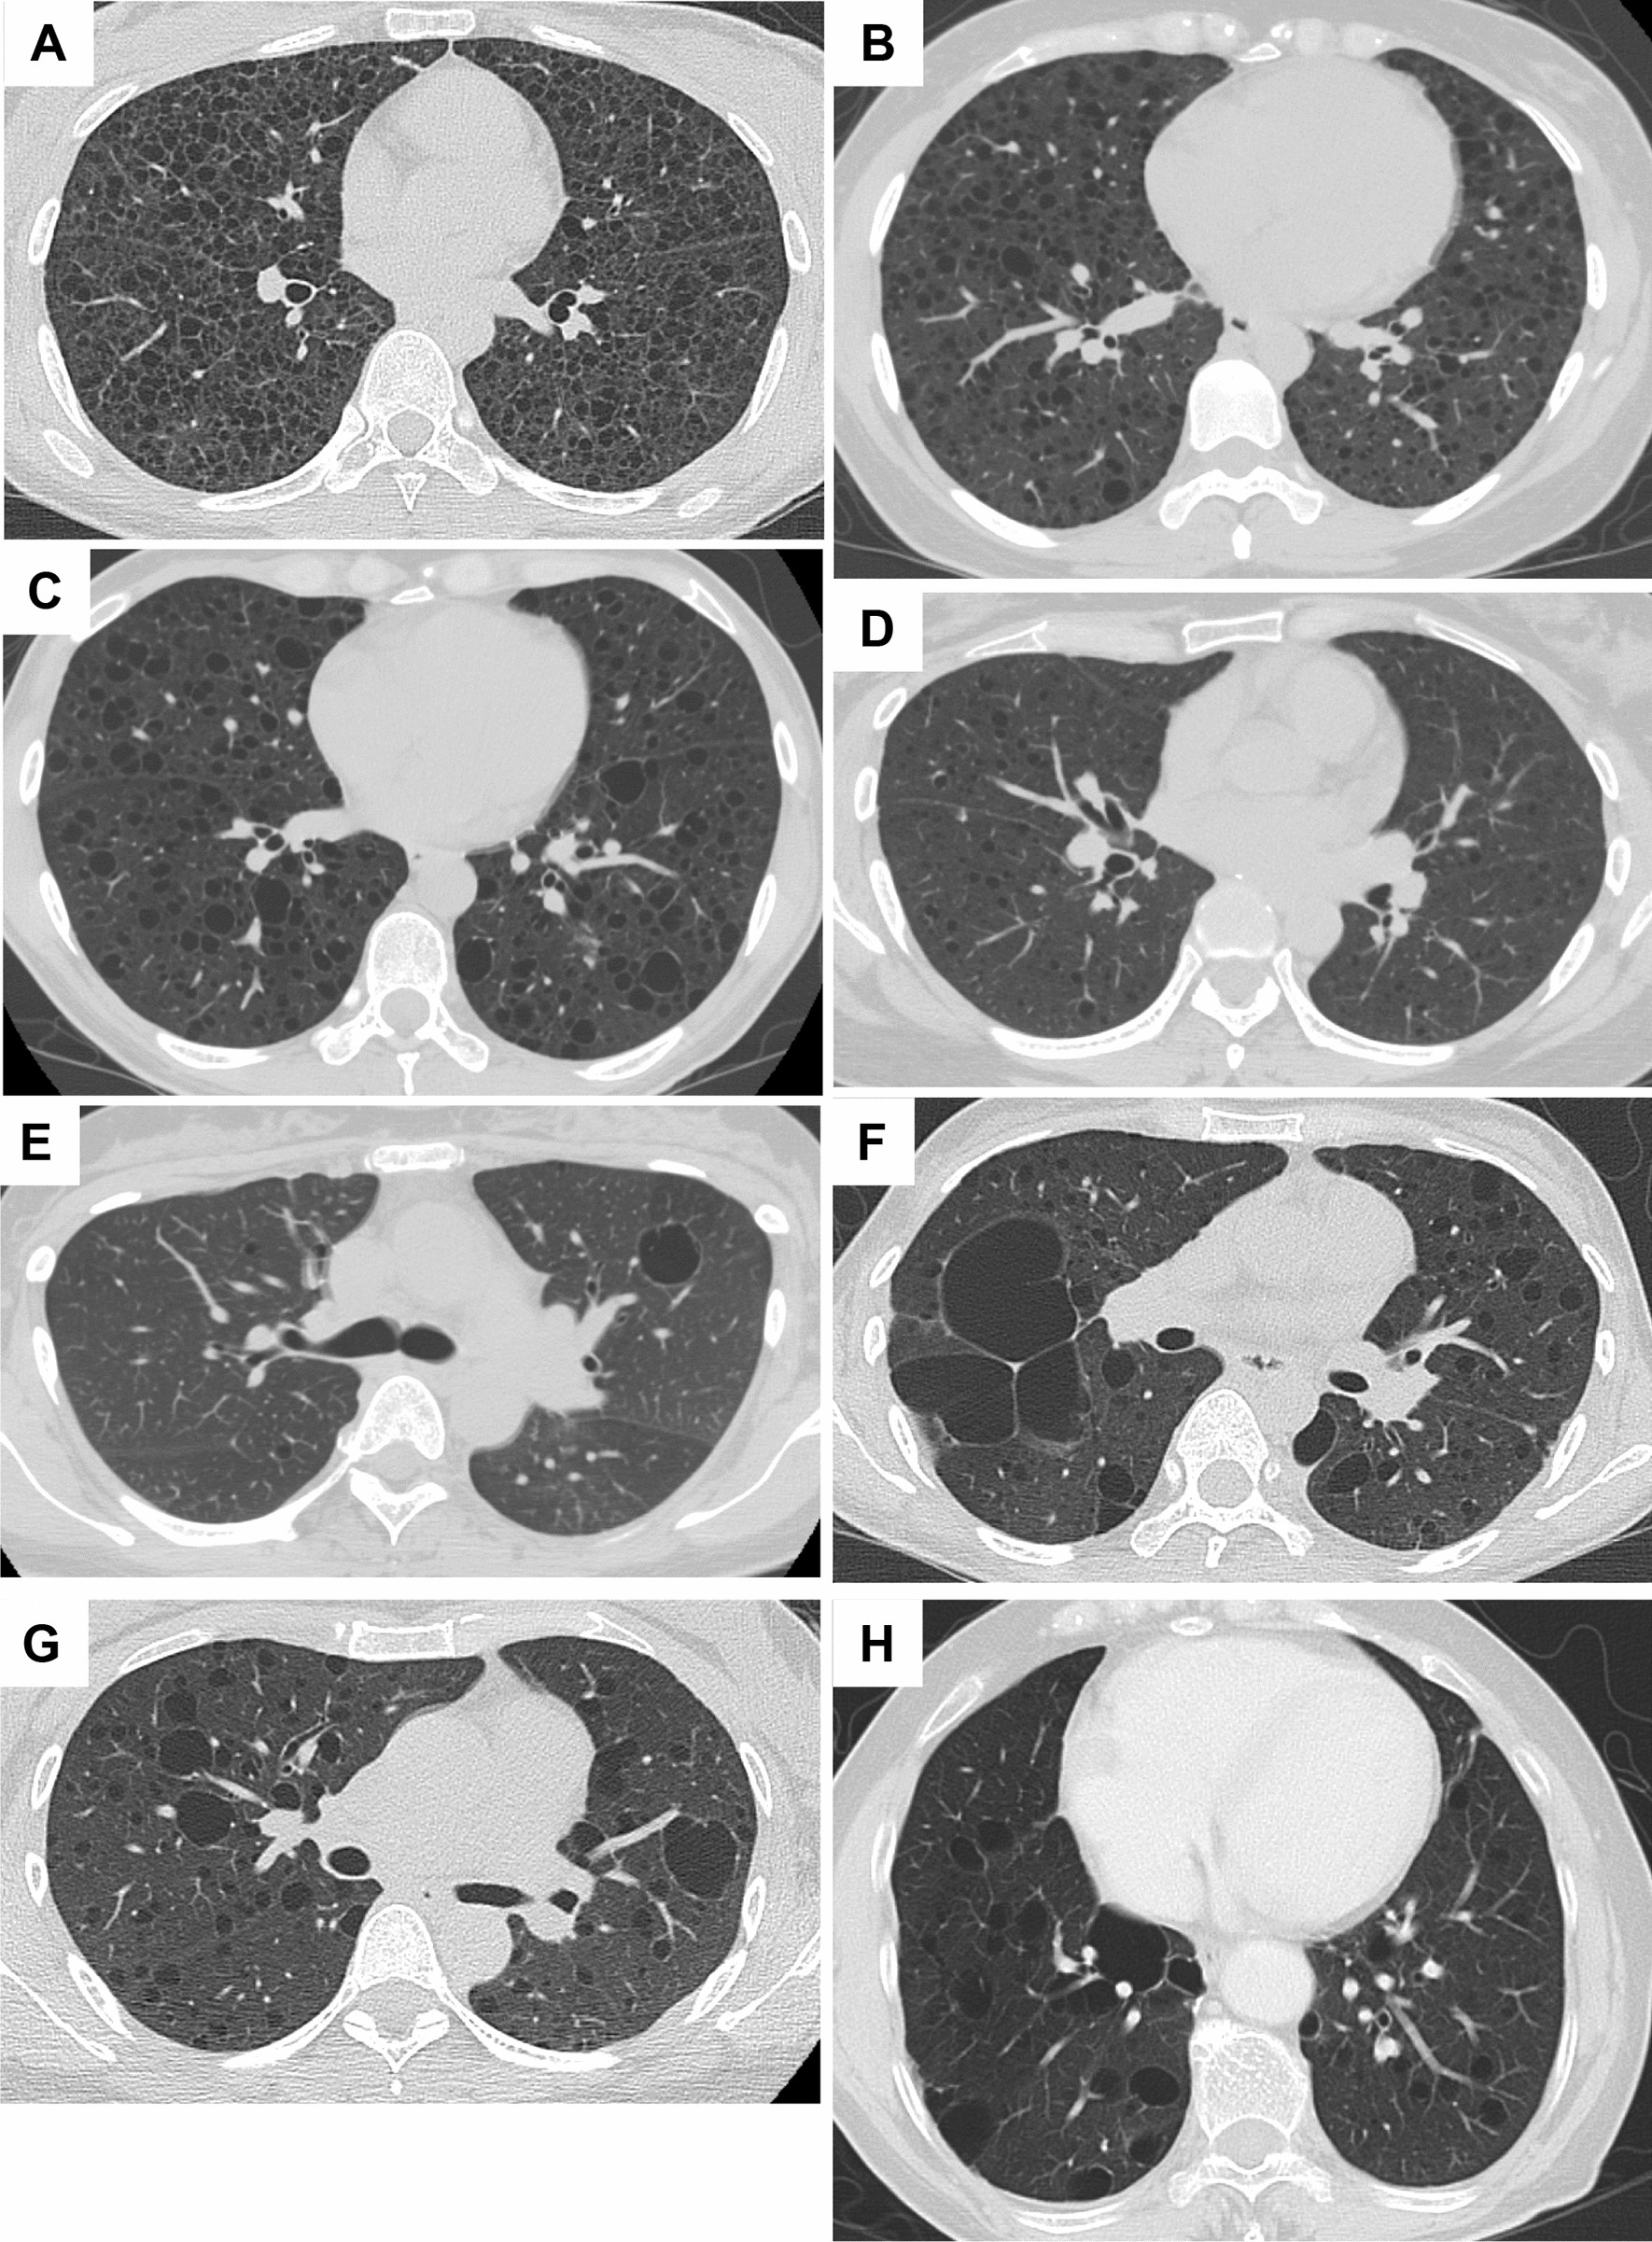

Figure 1

Representative HRCT images of common cystic appearance alone or with co-existence of large cysts. (A) A 32-year-old female with S-LAM whose diagnosis was established by transbronchial lung biopsy (TBLB). Numerous pulmonary cysts are noted. (B) A 33-year-old female, clinically diagnosed as having S-LAM with moderate to severe cyst formation. (C) A 45-year-old female with S-LAM, diagnosed by lung biopsy, showed mild cyst formation. (D) A 39-year-old female with S-LAM, diagnosed by lung biopsy, showed very mild cyst formation. (E) A 39-year-old female with S-LAM. Cyst formation was very mild but included a large cyst. She had a history of right pneumothorax and LAM was diagnosed by lung biopsy. (F) A 38-year-old female with S-LAM. Large irregularly shaped cysts were observed in the right lung along with the pathognomonic cystic appearance. She had bilateral pneumothoraces simultaneously and the diagnosis was made histopathologically. (G) A 41-year-old female with S-LAM. Abnormality on chest roentgenogram was discovered at a regular health check-up and the diagnosis was made by lung biopsy. Several large cysts were seen in both lung fields. (H) A 71-year-old female with S-LAM. She had a right lower lobectomy due to lung cancer, but the co-existence of LAM in underlying lung tissue was not recognized. Large cysts were observed more frequently in the remaining right lung than the left lung.